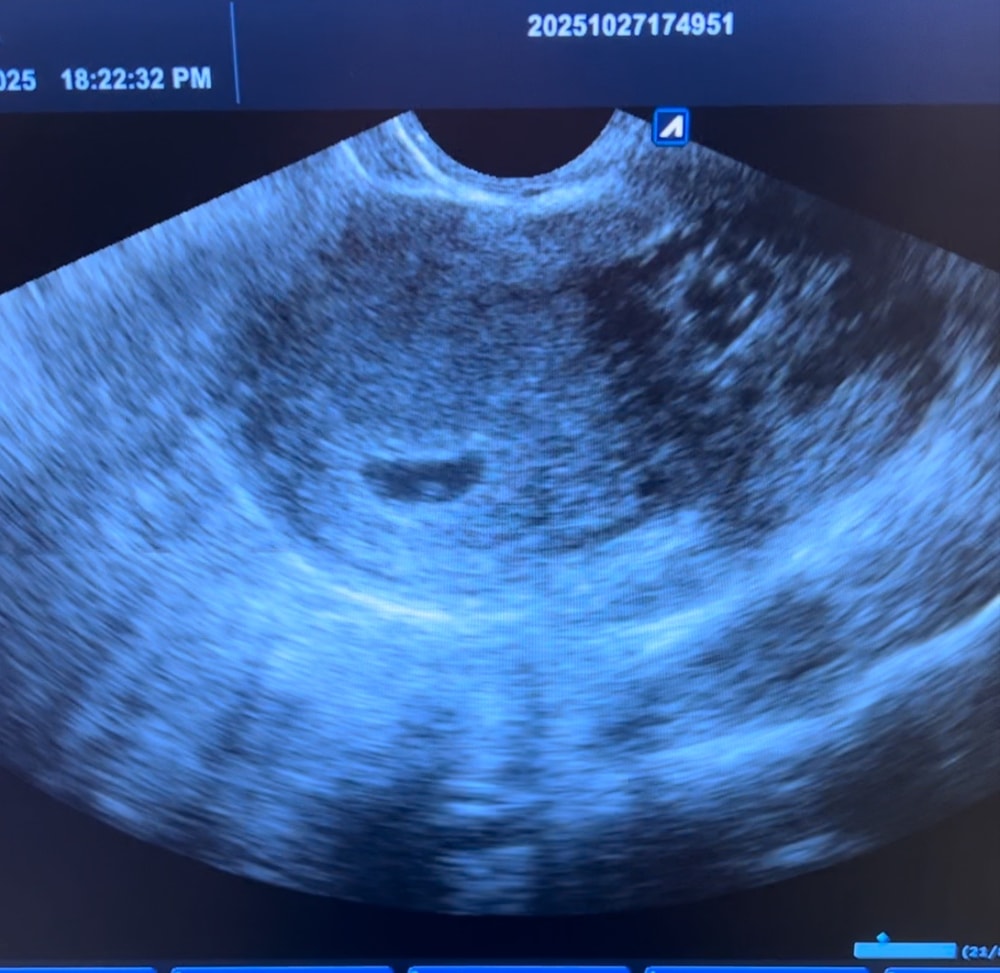

Как минимум плодное яйцо и желточный мешочек ) но статичному кадру плохо понятно, но если в динамике может уже мерцание сердечка было ? У эмбриончика . Тут не совсем хорошее качество узи)

Череппааашка по имени Натааашка , увидели пульсацию как мне сказали это был желточный мешочек, аппарат узи был достаточно старый, качество изображения не очень хорошее

Виктория Рыгина, ну пульсация только у эмбриона может быть ) у мешочка никак нет 😅эмбрион обычно сливается с контурами жм на ранних сроках и если аппарат плохой тяжело увидеть эти 0,5 мм . Через неделю уже точно подрастет )

Череппааашка по имени Натааашка , так то даже про эмбрион сказали что не понятно есть он или нет, контроль через неделю, очень переживаю